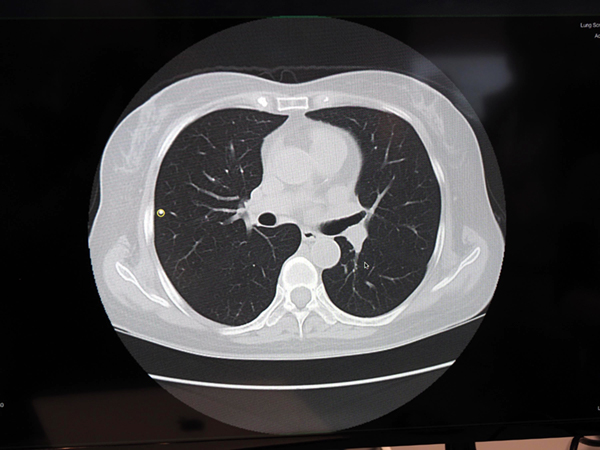

エルピクセルは,前回のMachine Learning Showcaseでは,脳のMR画像から脳動脈瘤を検出する技術を紹介したが,今回はさらに領域を広げ,スクリーニングと救急の2つのカテゴリに分けて,デモンストレーションを行った。スクリーニングでは,脳動脈瘤の検出に加えて,白質病変のセグメンテーションや脳計測,胸部CTと胸部単純X線撮影,マンモグラフィの病変検出を紹介した。また,救急では,整形外科領域の単純X線撮影での骨折の検出技術を披露した。また,展示以外では,学会では,脳動脈瘤検出による読影精度を評価に関する発表も行われている。このように着実に事業を拡大しているエルピクセルであるが,2019年中にはFDAにAIソフトウエアの申請を行うとしており,そのための準備を進めているという。また,日本国内では,2018年10月から11月にかけて,オリンパス,富士フイルム,キヤノンメディカルシステムズが同社に出資するとアナウンスしている。今や日本を代表する医療AI企業となった同社の動きには,今後も注目していく必要がありそうだ。

エルピクセルが開発する胸部CT画像の病変検出技術